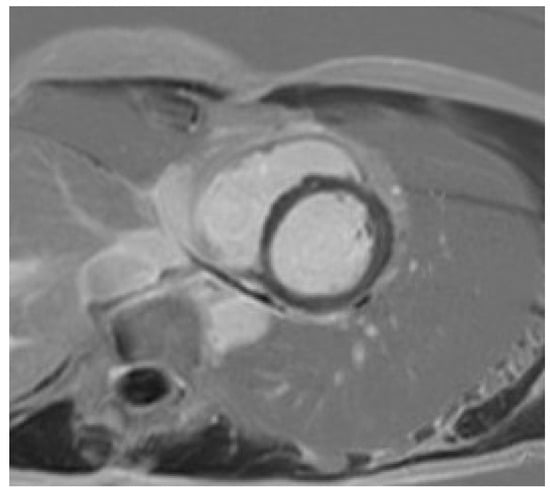

Certain subtle structural abnormalities (focal LV hypertrophy [54], mitral valve leaflet abnormalities [55], abnormal papillary muscle morphology and insertion [55], myocardial crypts [56]), which may be suggestive of early cardiomyopathy are easily missed with an echocardiography-only approach. The presence of interstitial and replacement fibrosis is also only established with cardiac MRI (Figure 2). This is especially important in athletes with an abnormal ECG who have a family history of NDLVC. The presence of a high T1 on a pre-contrast mapping sequence may be suggestive of extracellular volume (ECV) expansion and early cardiomyopathy. A high T1 should however always be interpreted in the clinical context; this finding when present in isolation is often of no clinical relevance [12]. Focal or diffuse replacement fibrosis in the absence of ventricular dilatation or dysfunction is also typical of certain genetic variants like FLNC, DSP, or Plakophillin-2 [PKP2]).

Figure 2. A mother presents to clinic for screening following the sudden death of her son who was a long-distance runner. Autopsy confirmed hypertrophic cardiomyopathy (HCM) secondary to a pathogenic TNNT2 variant. The victim’s uncle was also diagnosed with HCM in the interim and referred for transplantation. The mother was a carrier for the TNNT2 variant. The ECG was abnormal; echocardiography was normal. CMR identified mid-wall fibrosis in the lateral wall, despite the absence of left ventricular hypertrophy.